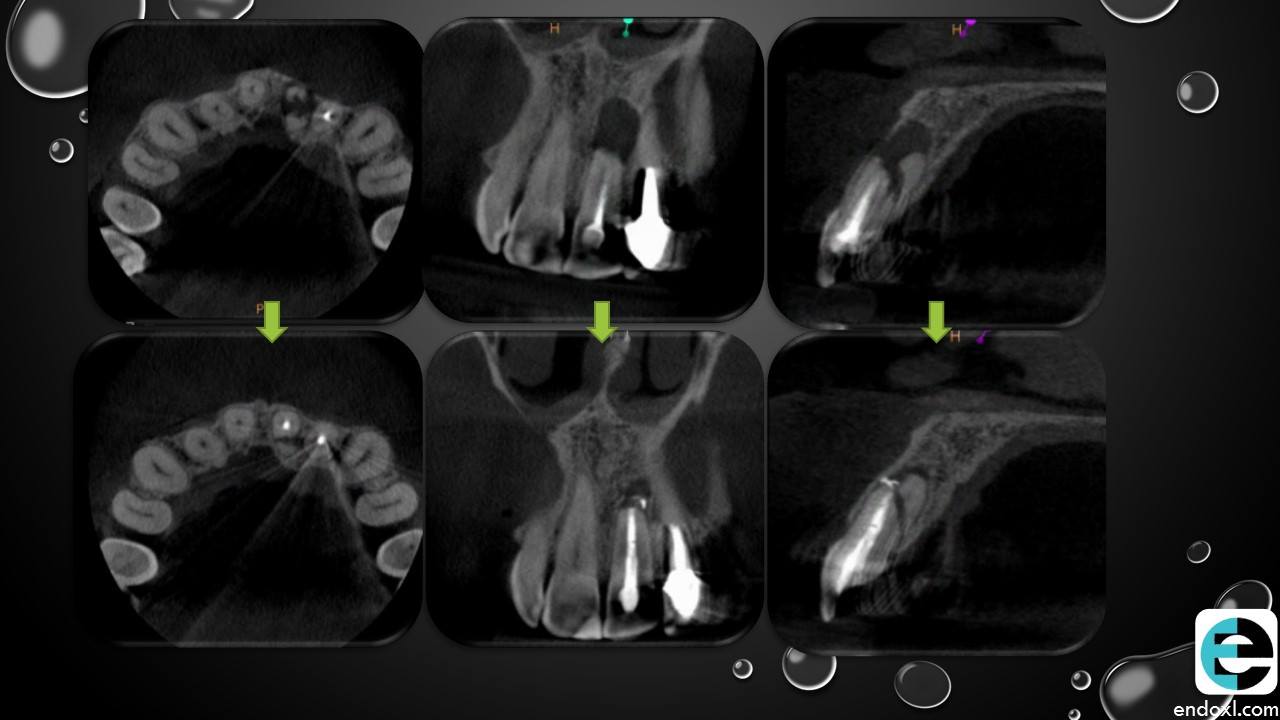

Wow, interesting case study on horizontal dental fractures! Short-term follow-up is crucial. Did you consider pulp vitality testing and potential complications like root resorption? For those bored during the healing process, Uno Online is a great distraction! Understanding long-term management strategies is key for successful outcomes. Thanks for sharing!

To determine the extent of the fracture, look for root involvement, and analyze the surrounding bone integrity, get periapical radiographs bitlife. Make sure the fracture line is clearly visible, and look for any indications of sequelae such periapical pathology or pulp necrosis.